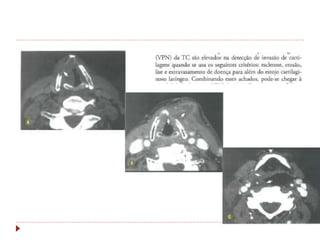

Laringe  Achados clínicos Rouquidão  Tosse crõnica, dispneia, disfagia.  CEC: 95-98%  60% na glote  30-40% supraglote  <5% subglote  Tabagismo e etilismo

 CEC: 95-98%

 60% na glote

 30-40% supraglote

 <5% subglote

 Tabagismo e etilismo